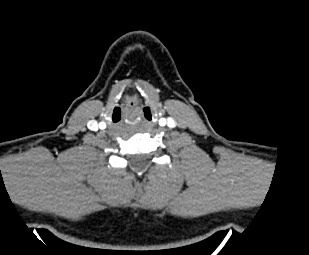

Мультиспиральная КТ сосудов шеи (КТ-ангиография) включает в себя сканирование брахиоцефальных артерий, то есть как сосудов кровоснабжающих головной мозг, так и проксимальные отделы плечевых артерий. Это крупные сосуды, которые отходят от дуги аорты и, разветвляясь, уходят в полость черепа. К ним относятся: брахиоцефальный ствол, общие, наружные и внутренние сонные артерии, подключичные и позвоночные артерии.

В наших медицинских центрах диагностика патологии магистральных сосудов шеи проводится на современных мультиспиральных компьютерных томографах экспертного уровня TOSHIBA AQUILION. Компьютерная томография относится к лучевым методам исследования, то есть для получения изображения внутренних органов используется рентгеновское излучение. Трубка томографа при помощи рентгеновских лучей послойно сканирует область исследования с минимальной толщиной среза от 0,5 мм, затем полученные данные трансформируются в объемные изображения. Оснащение аппаратов позволяет получать снимки и трехмерные реконструкции сосудистой системы превосходного качества, при этом пациент получает минимальную дозу облучения.

Для улучшения визуализации сосудистой системы обязательным является проведение контрастного усиления. Для этого пациенту внутривенно вводится йодсодержащий контрастный препарат, который активно поглощает рентгеновские лучи и обеспечивает яркую видимость даже мелких сосудов на фоне окружающих тканей.